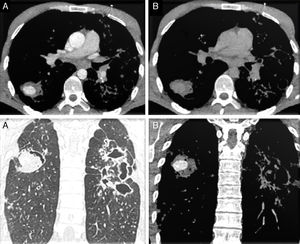

Cortes axiales de TC en ventana de mediastino: lesión en el LID, de bordes bien definidos, con captación de contraste en fase arterial (A superior) y lavado en fase venosa (B superior). Cortes coronales de TC en ventana de parénquima (A inferior) y en ventana de mediastino (B inferior) en fase arterial: lesión nodular captante en LID e imágenes de bronquiectasias y cavitaciones extensas en hemitórax izquierdo.

Varón de 33 años, rumano, que acudió al servicio de urgencias de nuestro hospital por cuadro de tos y hemoptisis. Refirió fiebre de 48horas y sudoración nocturna de 2 semanas de evolución. Como antecedente señaló una tuberculosis (TB) pulmonar tratada hacía 5 años. El paciente asociaba clínica de distrés respiratorio. Con estos datos se realizó una radiografía de tórax identificándose una opacidad alveolointersticial bilateral. Posteriormente se efectuó una tomografía multidetector (TCMD) torácica con contraste (CIV) que mostró varias consolidaciones, algunas cavitadas, bronquiectasias extensas y una lesión redondeada bien definida de 3cm en el segmento apical del lóbulo inferior derecho (LID) que presentaba, en fase arterial captación de contraste y en fase venosa lavado del mismo (fig. 1). Estos hallazgos se interpretaron como afectación tuberculosa con una imagen de probable seudoaneurisma de Rasmussen.

La hemoptisis se expresa en el parénquima pulmonar como áreas en vidrio deslustrado y áreas de atelectasia obstructiva por ocupación hemática bronquial, pero estos son signos inespecíficos3. La identificación de una imagen nodular que capta intensamente contraste en fase arterial y que en la fase venosa presenta fenómeno de lavado hace sospechar este tipo de lesión vascular.